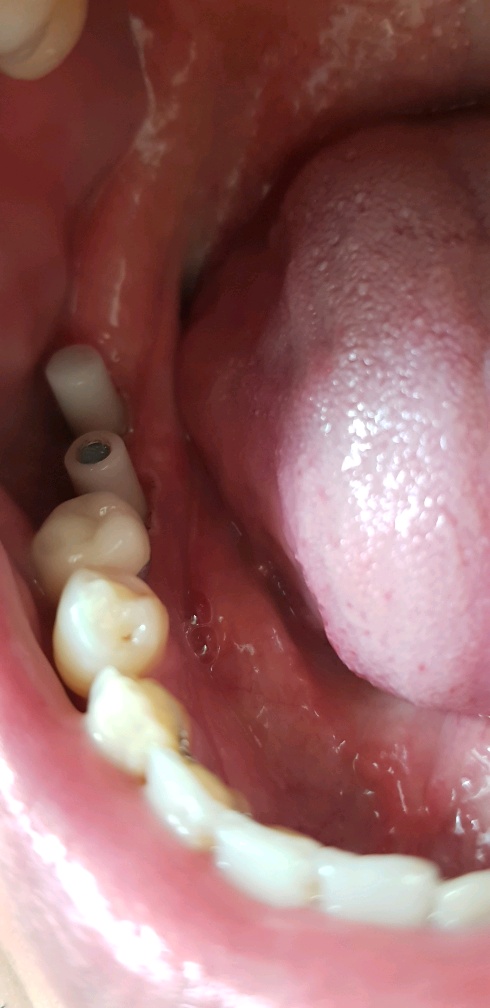

이건 2번째 방문한 오늘 박아놓은 임플란트다.

다음주 화요일에는 정말 치아를 올린다고 한다.

그땐 마취 놓는 것도 없고, 아프지도 않다고 한다.